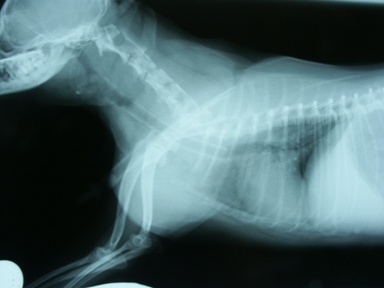

処置:自作シリコンステント(図5)、Wallstentに交換、さらに前方に1本追加(図6)。

図6 症例1の第371病日。ステント前方再虚脱し、同サイズのWallstentを前方に1本追加。